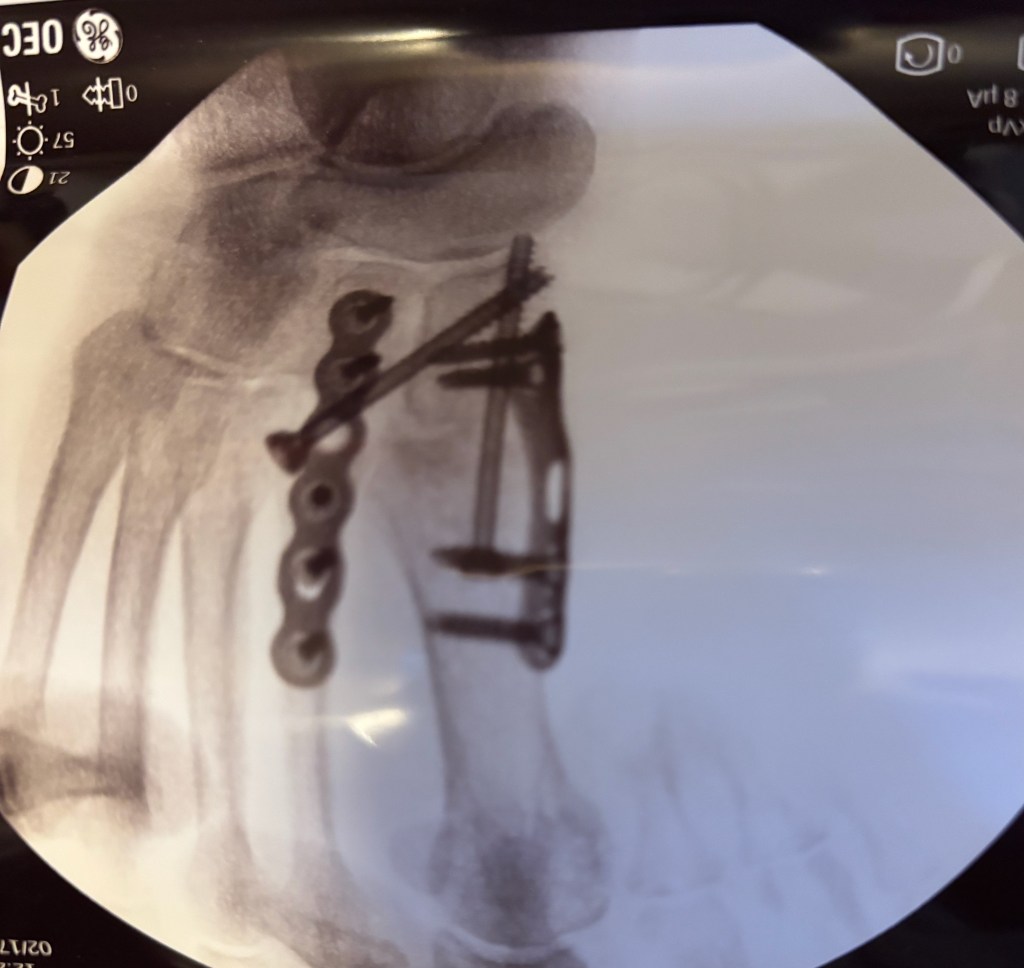

I thought about showing physical pain from peripheral neuropathy. I thought about showing pain from the surgery I had to put my foot back together after I broke it, and the marbles I have to pick up with my toes. The marbles are part of the physical therapy that will strengthen my arch. The foot looks weird because when I broke my foot, the arch collapsed. After the surgery, my food is weird looking.

The brown, oblong things with the holes are the plates attached to my bones. The silver thing is the screw that holds the plates in place. The screw may or may not be removed in a few months. The triangles are like the pain from the neuropathy. Sometimes sharp, sometimes dull. The coral round things are the marbles I need to pick up with my toes.

Surgery left me with a foot that looks like it merged with an erector set. I no longer have pain from the surgery, but I do have pain from the fallen arch of my foot.